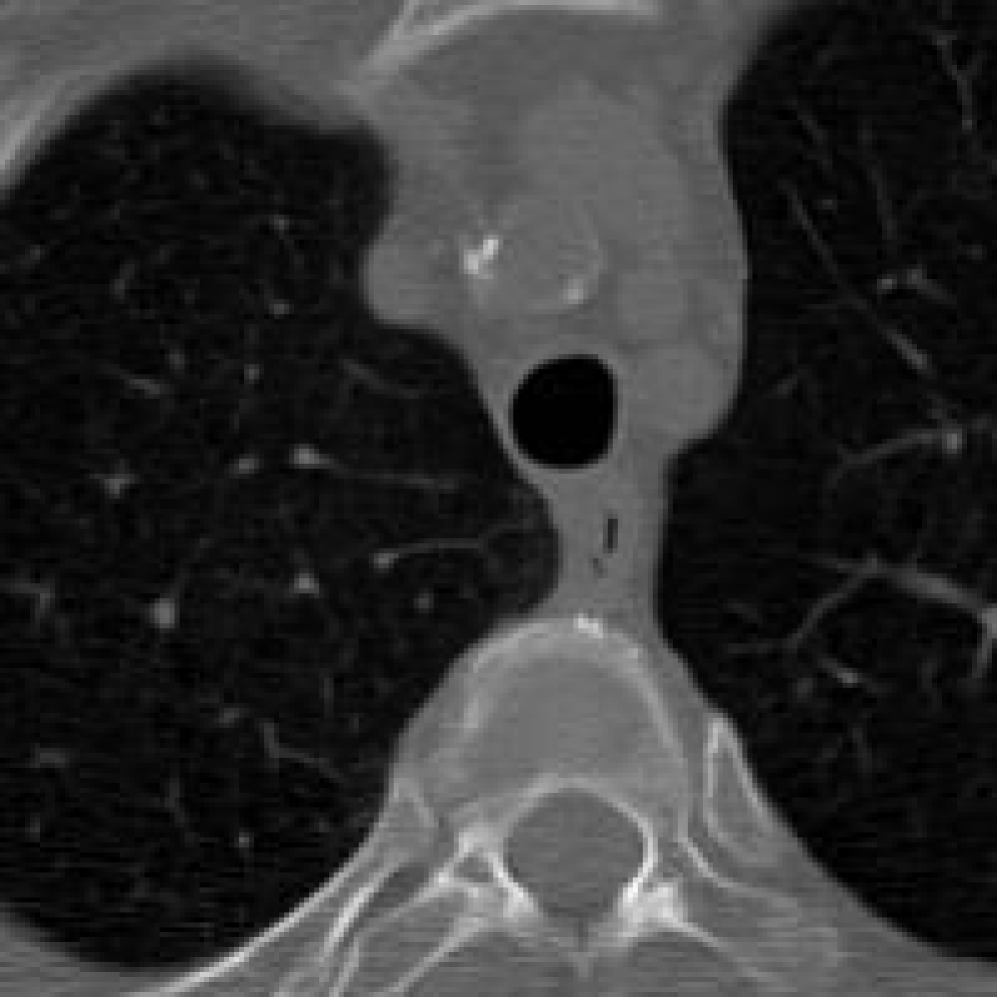

Figure 10: The visual comparison of different compression methods on a CT Heart Segmentation image.

Figure 11: Zoomed-in view of the highlighted region in Figure 10.

Figure 12: The visual comparison of different compression methods on another CT Heart Segmentation image.

Figure 13: Zoomed-in view of the highlighted region in Figure 12.

IV-B3 Visual Comparison

Figures 7 and 8 present representative examples from the CIL dataset and their zoomed-in regions, respectively. For the CT Heart Segmentation dataset, Figures 10 and 12 illustrate typical reconstruction results, while Figures 11 and 13 further enlarge local regions to compare structural details. Across both datasets, COLI preserves fine structures and global continuity well even at relatively low bpp. Specifically, on the CIL dataset, COLI attains the lowest bitrate among INR-based methods while still maintaining clear texture details. On the CT Heart dataset, COLI also operates at a low bpp within the INR family and delivers superior visual quality with improved detail fidelity and smoother structural presentation. The zoomed-in regions show fewer blocking artifacts and smoother transitions, making COLI especially suitable for large images and medical images. These visual results validate that INR-based compression can achieve efficient storage with reliable perceptual consistency, offering practical advantages for real-world large-scale image processing.